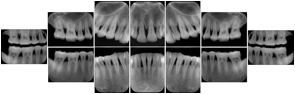

Intra-oral radiography typically involves acquisition of multiple images of various parts of the dentition. Many digital radiographic systems offer customized templates that are used for displaying the images in a study on the screen. These templates may also be referred to as mounts or view sets. The Structured Display Object represents a standard method of encoding and exchanging the layout and intended display of Structured Displays. A structured display object created in this manner could be stored with a study and exchanged with images to allow for complete reproduction of the original exam.

1. A patient visits a General Dentist where a Full Mouth Series Exam with 18 images is acquired. The dentist observes severe bone loss and refers the patient to a Periodontist. The 18 images from the Full Mouth Series along with a Structured Display are copied to a DICOM Interchange CD and sent with the patient to see the specialist. The Periodontist uses the CD to open the exam in his Dental Radiographic Software and consults via phone with the General Dentist. Both are able to observe the same exam showing the images on each user's display using the exact same layout.

Intra-oral Full Mouth Series Structured Display

Figure OO-1. Intra-oral Full Mouth Series Structured Display